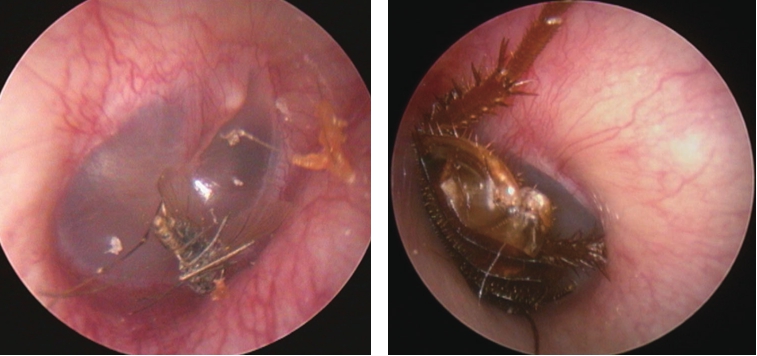

外耳道异物种类可分为动物性(如各类昆虫或爬虫类,图5-1)、植物性(谷类、豆类等,图5-2)及非生物性(如棉花、塑料、玻璃、纽扣电池、医用纱条等,图5-2)。Thompson等的一项回顾性研究揭示在162例外耳道异物中,棉花(22%)、昆虫(18%)和珠子(16%)是最常见的异物。异物可长时间滞留于外耳道,压迫周围组织,并可继发感染,最终导致局部组织炎症、坏死等,部分异物可被耵聍包绕形成耵聍栓塞。

图5-1 外耳道可见蚊子、蟑螂等小动物侵入